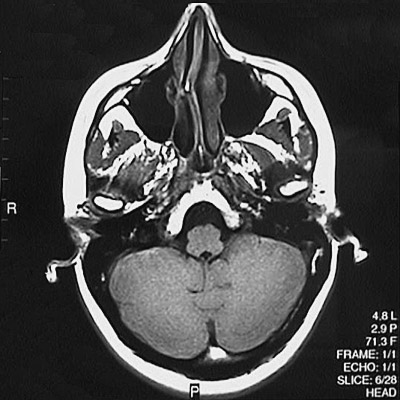

This is a normal axial T1 weighted MRI scan demonstrating the nasal septum and concha and maxillary sinus and sphenoid sinus and medulla and fourth ventricle and cerebellar hemisphere.